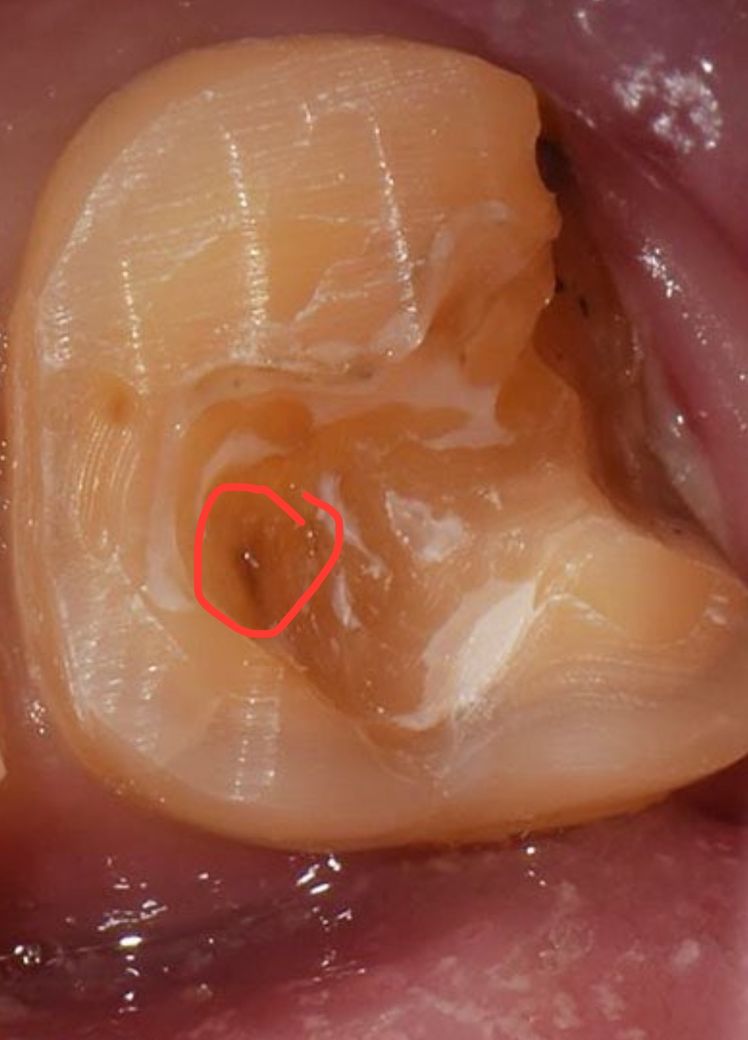

엑스레이 사진상 오른쪽 아래 이빨인데 때운거 떨어졌었다가 4년정도 방치했고 안에 살짝 반투명 회색-연한 반투명 검정 부분 있길래 충치인줄 알고 무조건 갈아낼거라 생각했는데 갈아내지도 않고 바람 몇번 쏘시면서 보시더니 매꿔도 될것같은데 바로 매꿔드릴까요? 하시고 매꿨어요.

마지막 사진은 예시 사진인데 표시한 부분 느낌처럼 되어있었습니다